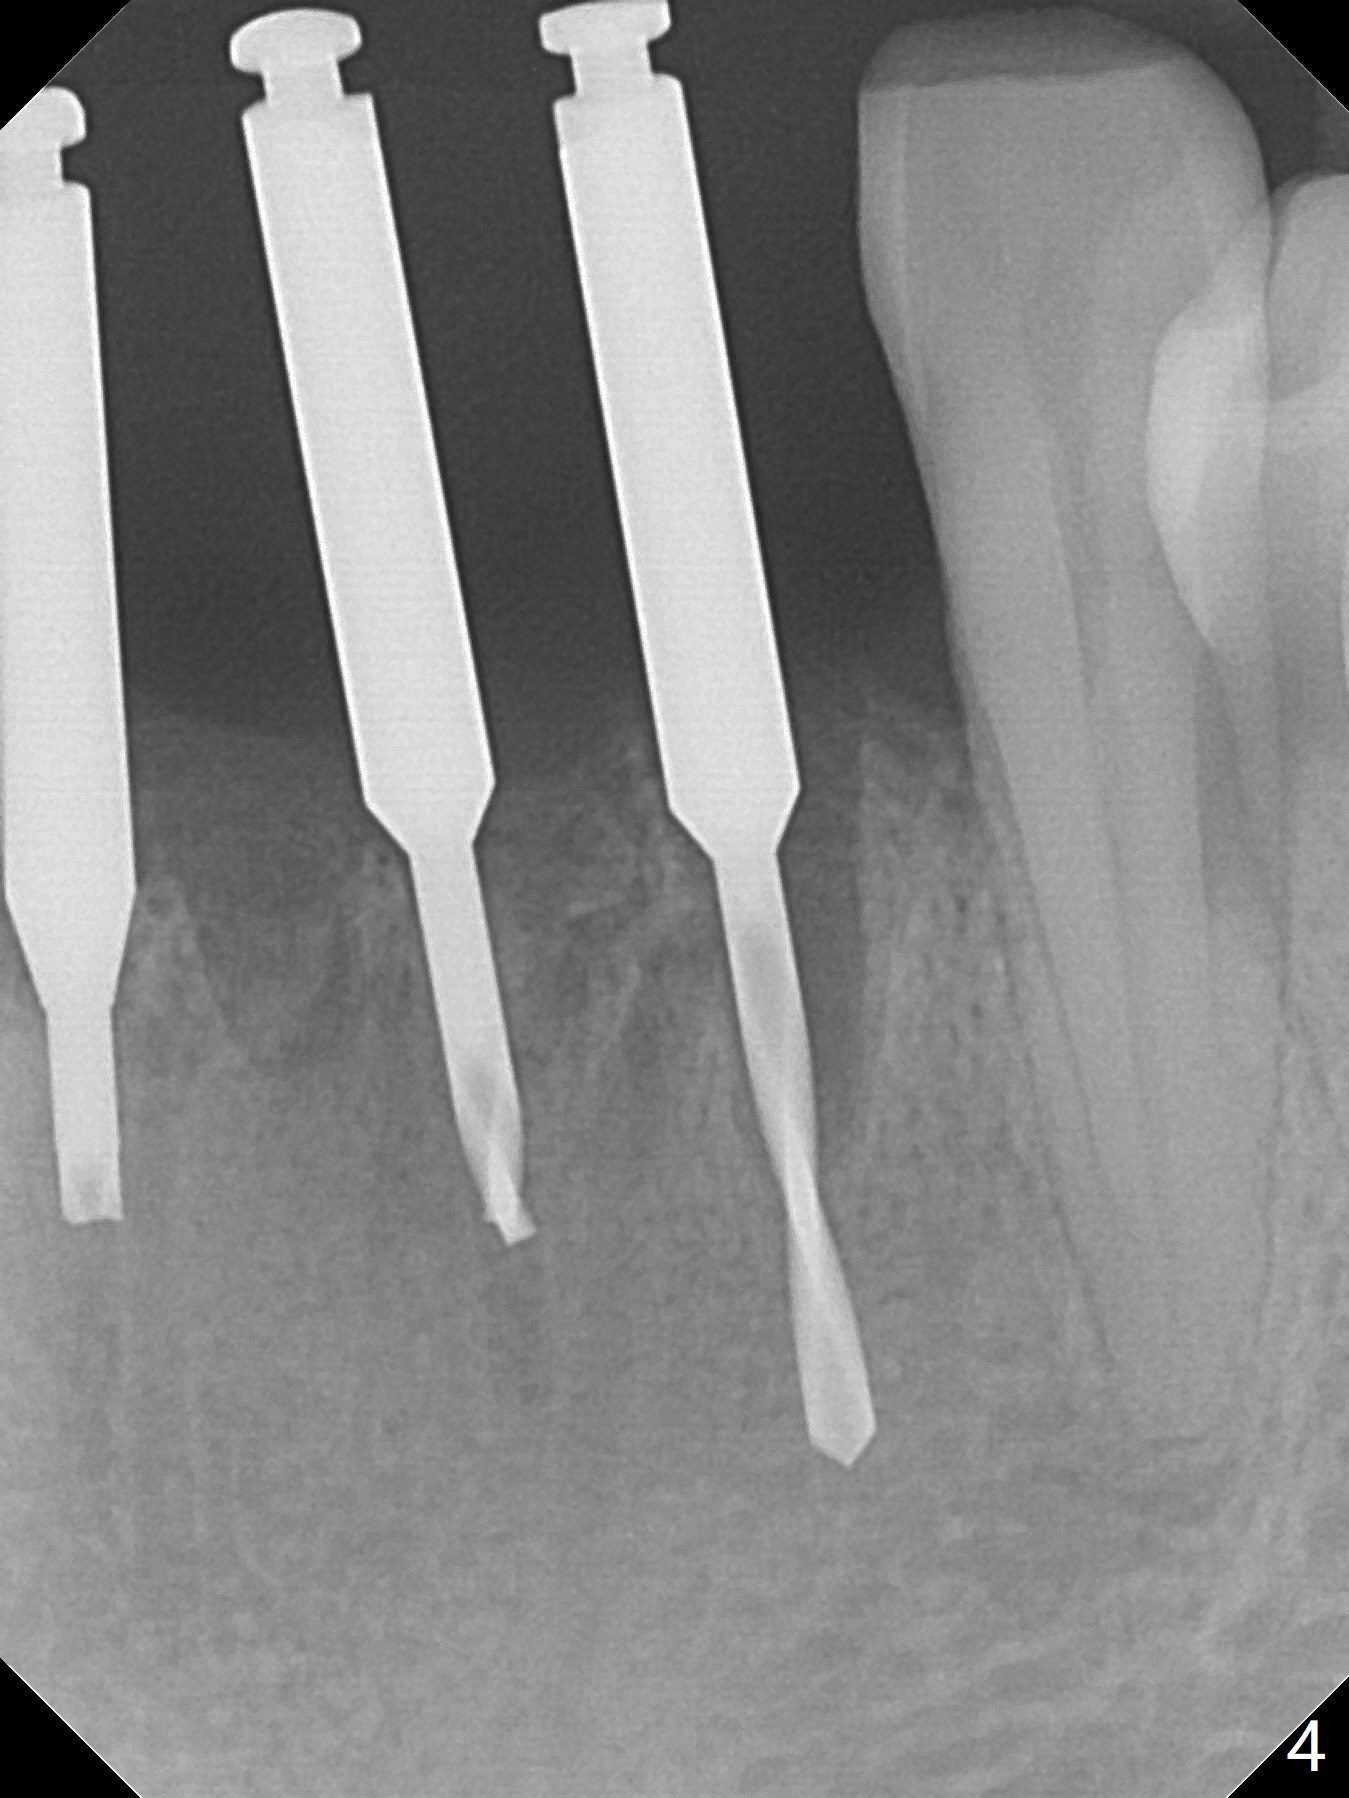

When the patient returns, the tooth #24 has exfoliated, while the ones at #25 and 26 has mobility III (Fig.1). The patient requests the tooth #23 extraction (Fig.2), but not #27. After SRP and extraction, osteotomy is initiated mesial to the sockets #23,25 and 26 (Fig.3,4) with intention to place 3 1-piece implants for 3 incisor crowns (Fig.5,6). Following Vanilla graft (Fig.5 *) a splinted provisional is fabricated to close the sockets (Fig.6). Peri-implant spaces close 5.5 months postop (Fig.7). Impression is taken after reprep for margin and parallelism (Fig.8). The final restoration consists of #23 single unit crown and #24-26 3-unit FPD (Fig.9). It appears that 2.5 mm 1-piece implants are not too small for the lower incisors (Fig.10-12), especially the central one (Fig.11). There may be perforation in the apical half of the lingual plate (L in Fig.10). The patient is not pleased with the shade of the #24-26 3-unit FPD (Fig.13 (6 months post cementation)). There is metal show through the abutments (*).